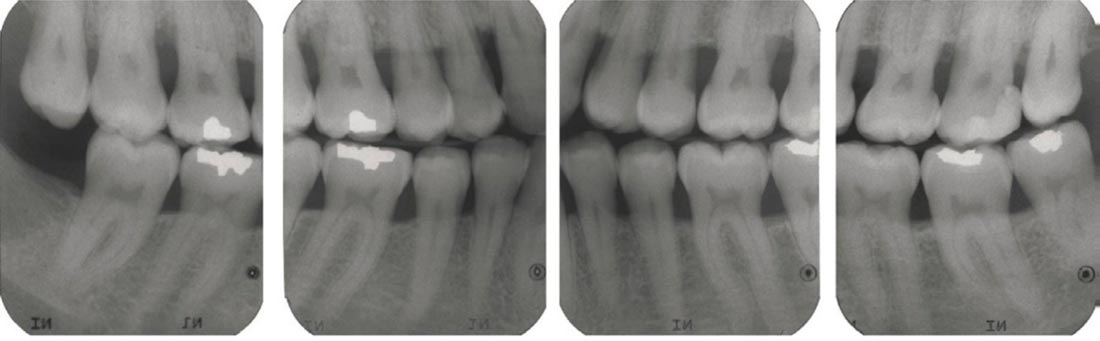

Зонування ПДЛ, холодовий тест, порівняльна перкусія, пальпація, дрілл тест, вибіркова анестезія, трейсинг, порівняння інформативності КТ та інтраорального тесту, правильні укладання для проведення якісних рентгенографічних досліджень, як своїми руками зробити позиціонер для інтерпроксимального знімка. Складні клінічні кейси, які потребують клінічного досвіду.